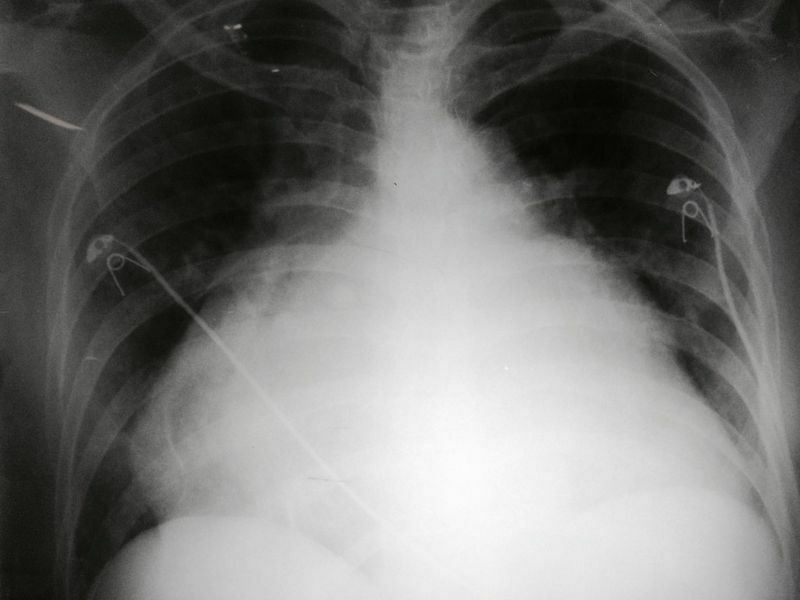

Quais são os achados radiológicos do aumento do AD? projeta-se mais para a direita e alarga-se +Cefalização do fluxo pulmonar (IC esquerda e estenose mitral) +Linhas B de Kerley (ao edema intersticial)

O que é o Sinal da borboleta? Quais são suas características radiológicas? Opacidade alveolar bilateral em campos pulmonares médios. -Diminuição simétrica da transparência pulmonar perto do hilo, poupando periferia -Significa edema alveolar extenso em edema agudo de pulmão/ICC. -Infiltrado que preserva a periferia.